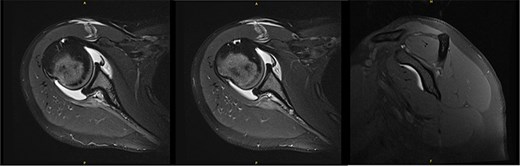

At 9.5 years, she presented reporting recurrent, progressive shoulder weakness and pain during external rotation during self-directed physiotherapy. There was visible atrophy of the right infraspinatus (Fig. 4). She had full symmetrical shoulder range of motion, with 4/5 strength of the right infraspinatus and a markedly weak Hornblower’s test.

Nine and half years after decompression, the patient presented with palpable and visible atrophy of the right infraspinatus.

New MRI arthrogram demonstrated no evidence of new or worsening SSN compression or other pathology. Imaging demonstrated increased right infraspinatus muscular tissue (Fig. 5), however, with significant continued fatty infiltration and persistent atrophy compared to the contralateral side.

MRI at 9.5 years after decompression demonstrated increased right infraspinatus muscular tissue.